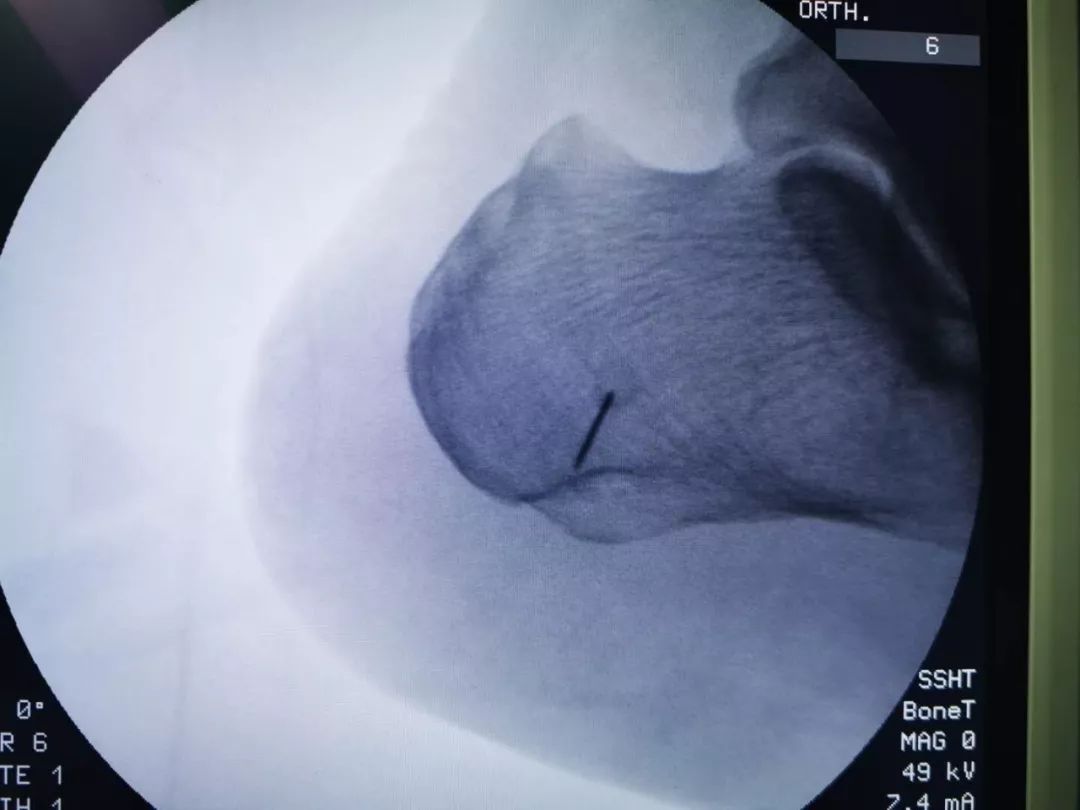

骨伤二科主任医师方磊经过与治疗团队认真讨论后,为患者制定了全新的微创手术方案,行关节镜下跟骨骨刺摘除术,手术取足跟部内侧两个0.5cm长小切口,在关节镜监视下切除增生骨赘,清理修整骨刺周围炎性组织,同时行跖筋膜松解,成功完成手术,目前患者术后恢复良好。